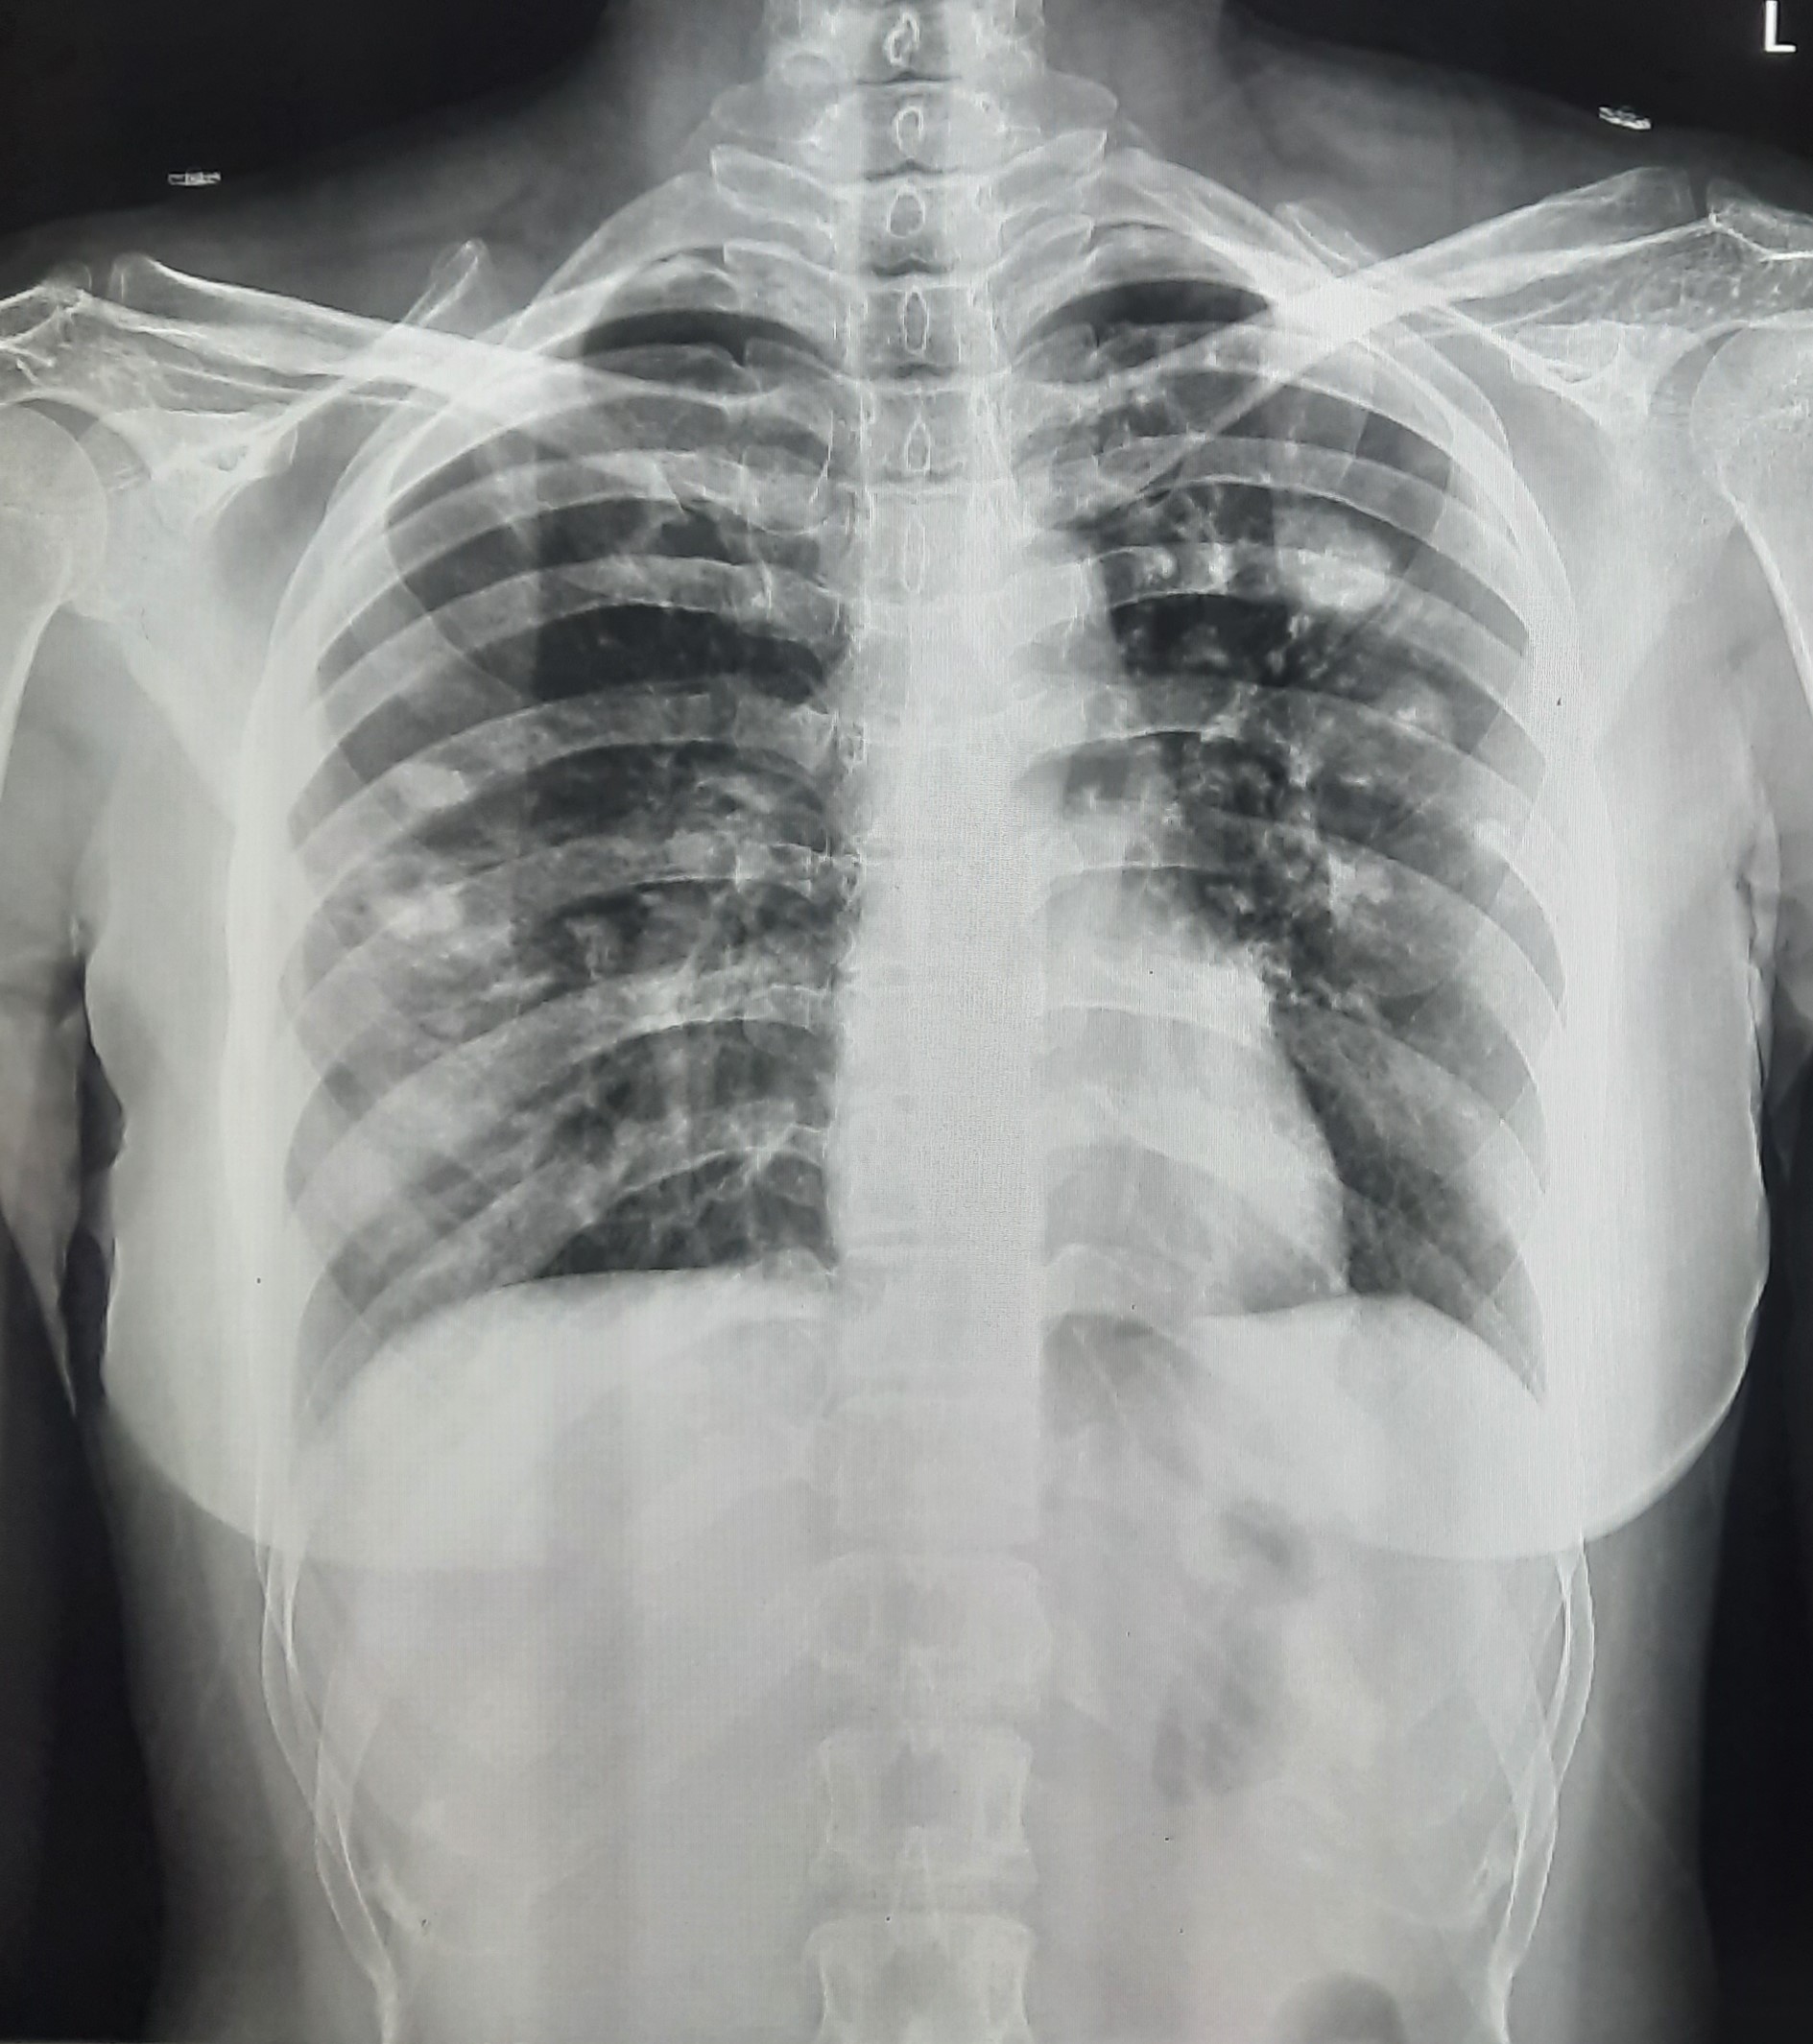

| 123 | IGGMC, Nagpur, Nagpur | P2 | 29-4349 | Dhammadip Wasnik | Consent taken on Paper | 35 Yrs. |

Provisional Diag : PTB Follow-up

Final Diag : Pulmonary Tuberculosis (Microbiologically Confirmed PTB) |

TB Case (Confirmed) | Abnormality visible on x-ray |